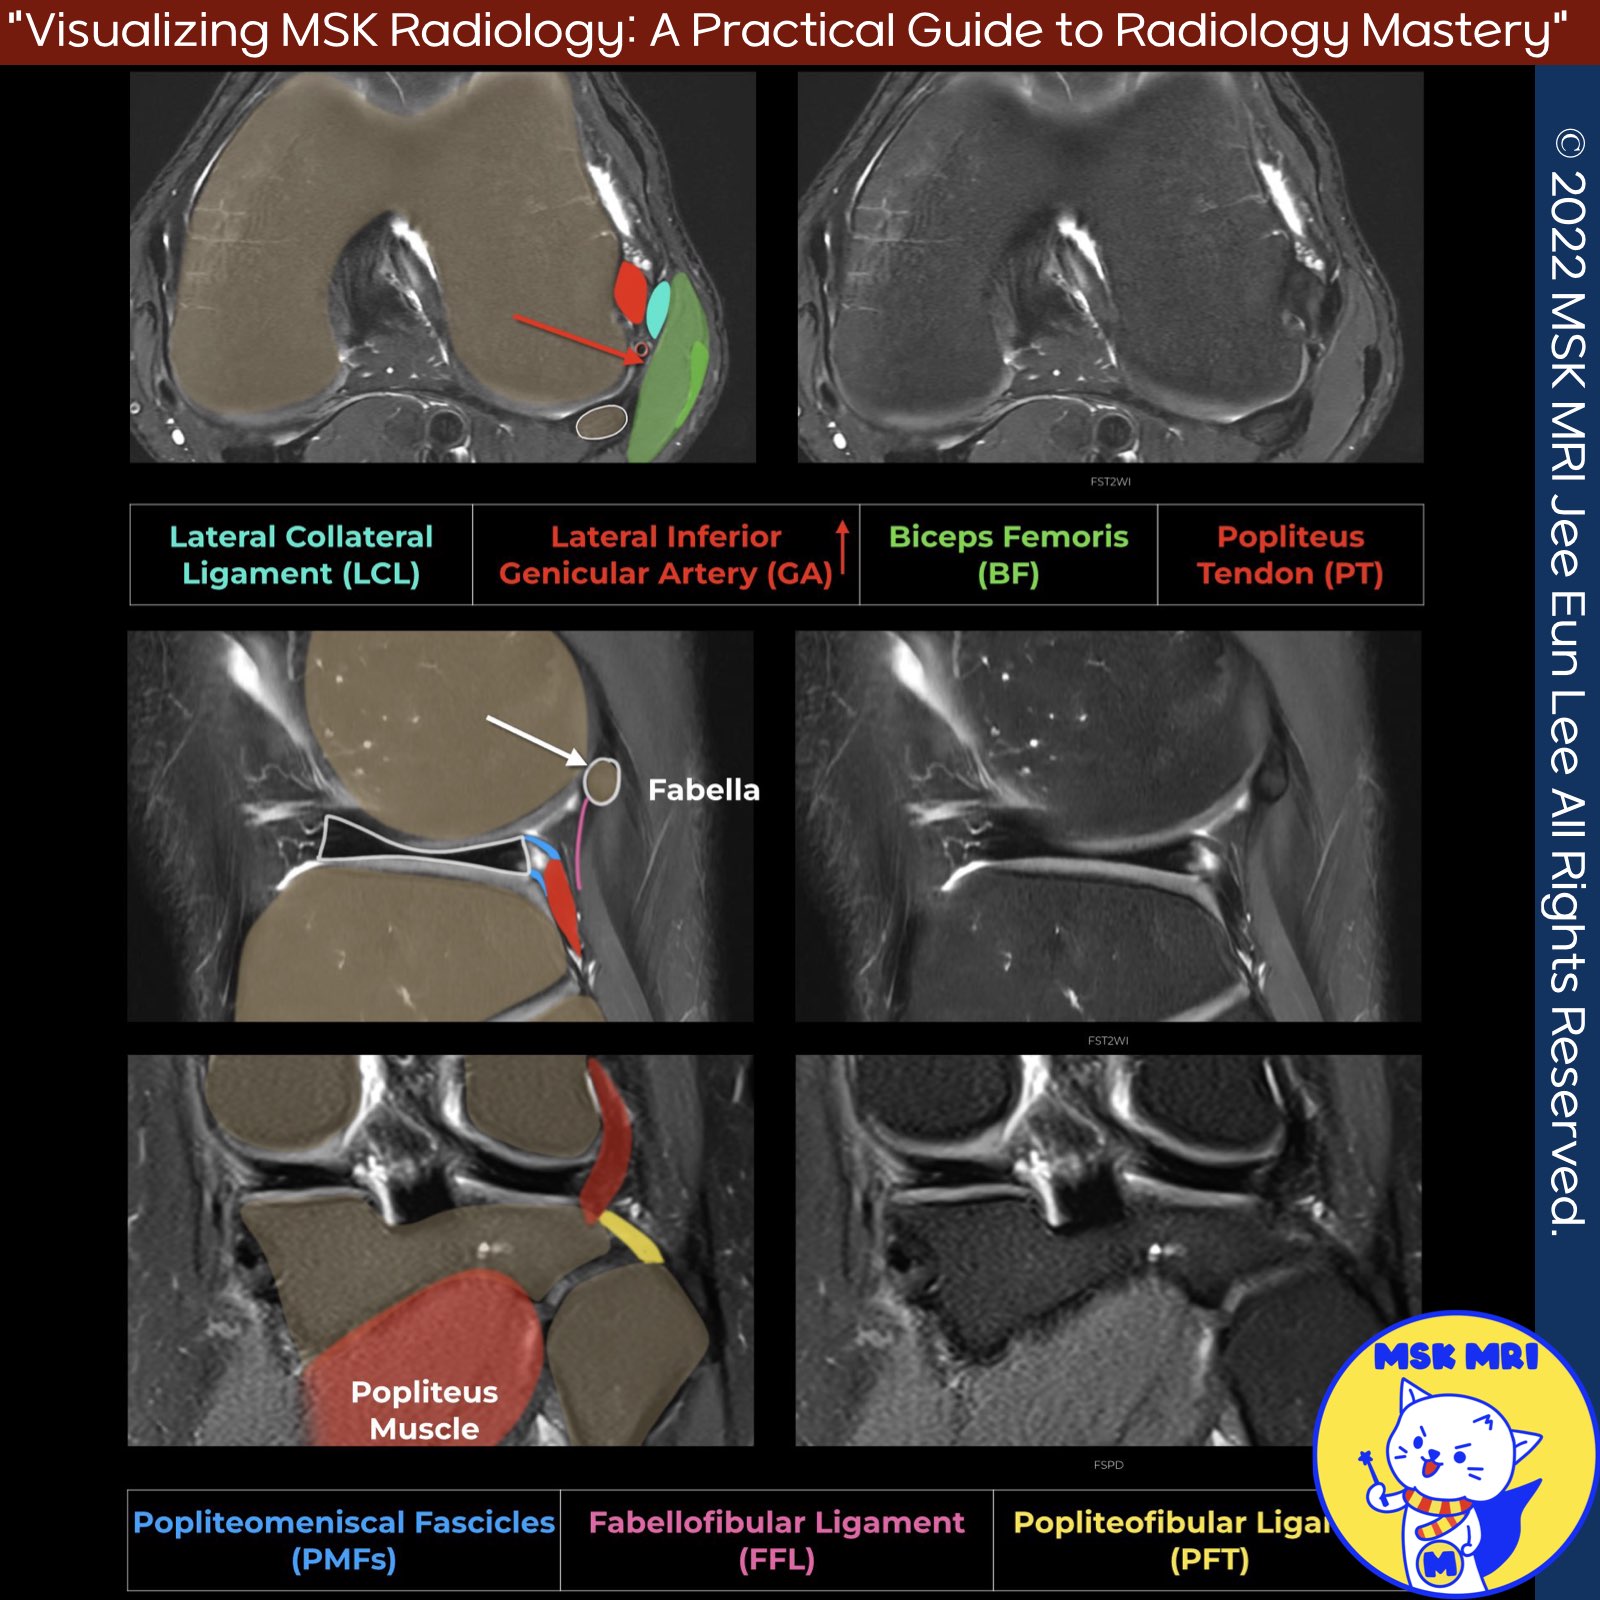

📌 Overview of Popliteus Musculotendinous Complex

The popliteus musculotendinous complex includes the popliteus tendon, muscle, and patellofemoral ligament. It provides resistance to external rotation during knee flexion and supports the posterior cruciate ligament by restraining posterior translation.

✅ Popliteus Tendon Pathway

The popliteus tendon travels through the popliteal hiatus, bound by popliteomeniscal fascicles, and moves underneath the posterolateral joint capsule and arcuate ligament to become extracapsular.

✅ Popliteofibular Ligament

The popliteofibular ligament runs from the popliteus tendon near the myotendinous junction to the fibular styloid process, located posteromedial to the biceps femoris and LCL insertion. It can be identified by locating the lateral geniculate vessels on coronal images.

✅ Popliteomeniscal Fascicles

The popliteomeniscal fascicles are divided into three components:

- Anteroinferior (yellow): Forms the lateral floor of the popliteal hiatus, merging with the popliteofibular ligament.

- Posterosuperior (red): Forms the roof of the popliteal hiatus, attaching to the posterior joint capsule above the popliteus tendon.

- Posteroinferior (purple): A controversial structure.

✅ Popliteus muscle insertion

The popliteus tendon passes under the fibular collateral ligament and attaches to the lateral femoral condyle.

The popliteus muscle attaches to the fibula through the popliteofibular ligament and inserts on the posterior surface of the proximal tibia, just superior to the soleal line.